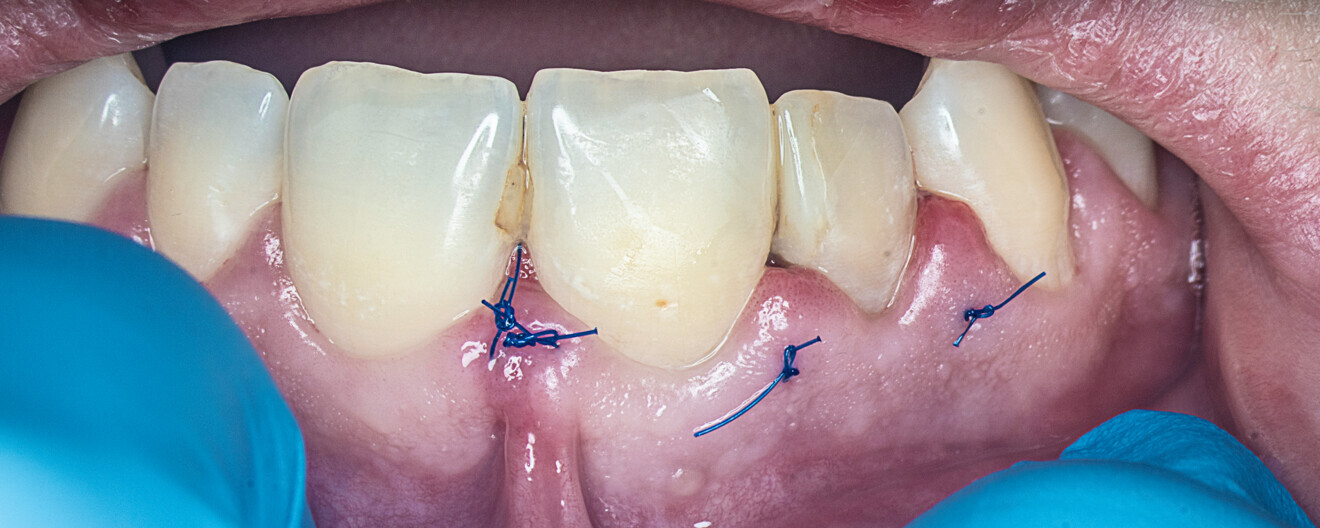

An incision was made from the maxillary left central incisor through the gingival sulcus to the right maxillary canine. After raising a flap, the granulation tissue was removed from the resorption cavity with a small excavator (Figs. 9–11). The root canal shaping protocol was performed with conventional chemomechanical preparation. The shaping sequence began with negotiation with passive hand files, followed by preparation with rotary files and irrigation using sodium hypochlorite with manual needle agitation. The irrigation protocol was performed as described in Case 1.

Figs. 9a & b: Clinical situation before the procedure (a) and after raising of the flap and perforation of the cortical bone (b).